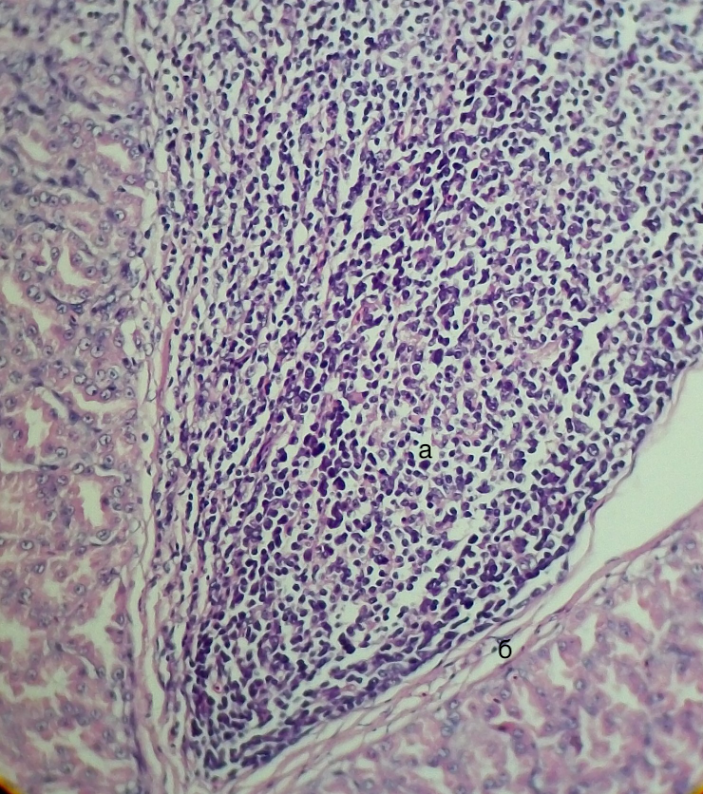

Рисунок 1 - Железистый отдел желудка утки кросса Агидель, слизистая оболочка

а – межэпителиальные лимфооциты, б – субэпителиально расположенные лимфоциты

Примечание: гематоксилин, эозин. Об. 15. Ок. 40